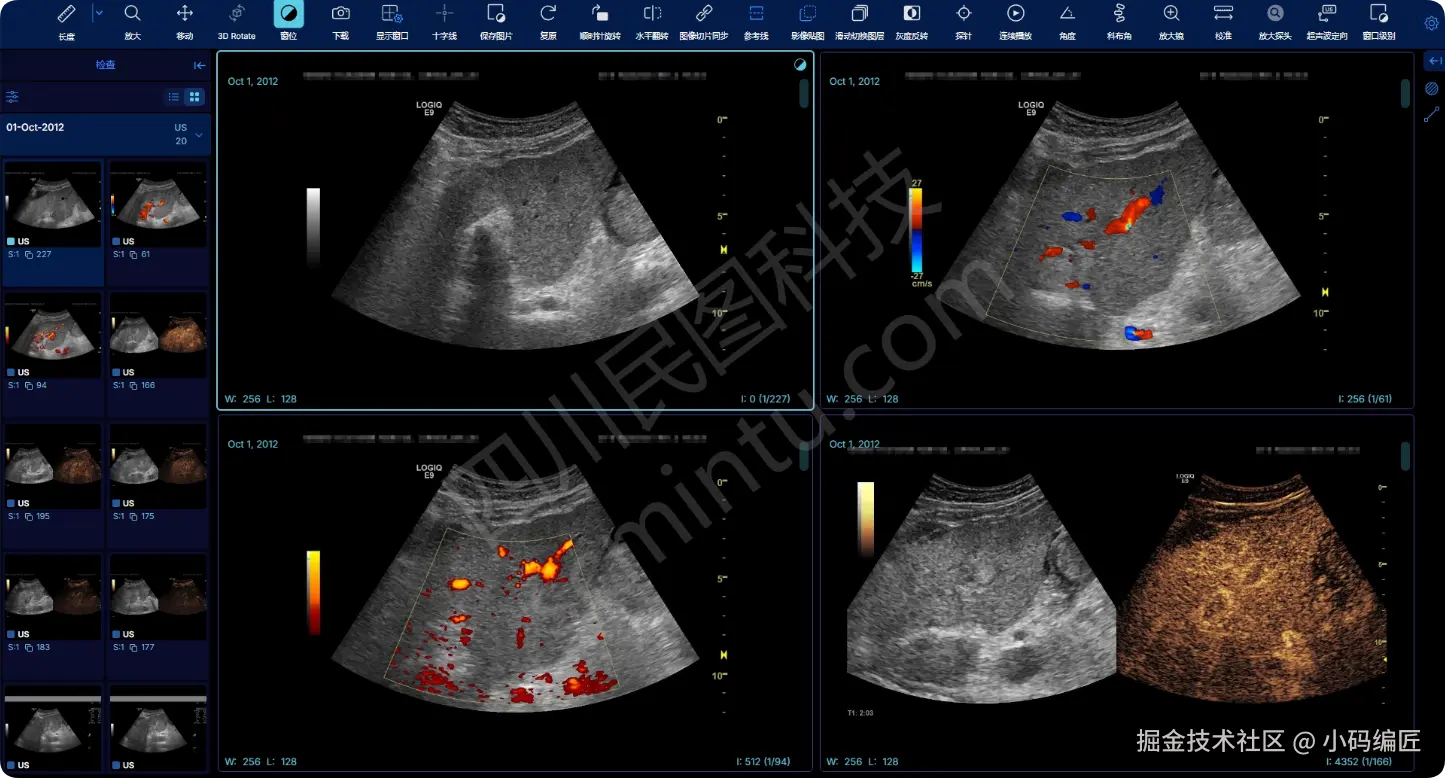

dicom管理